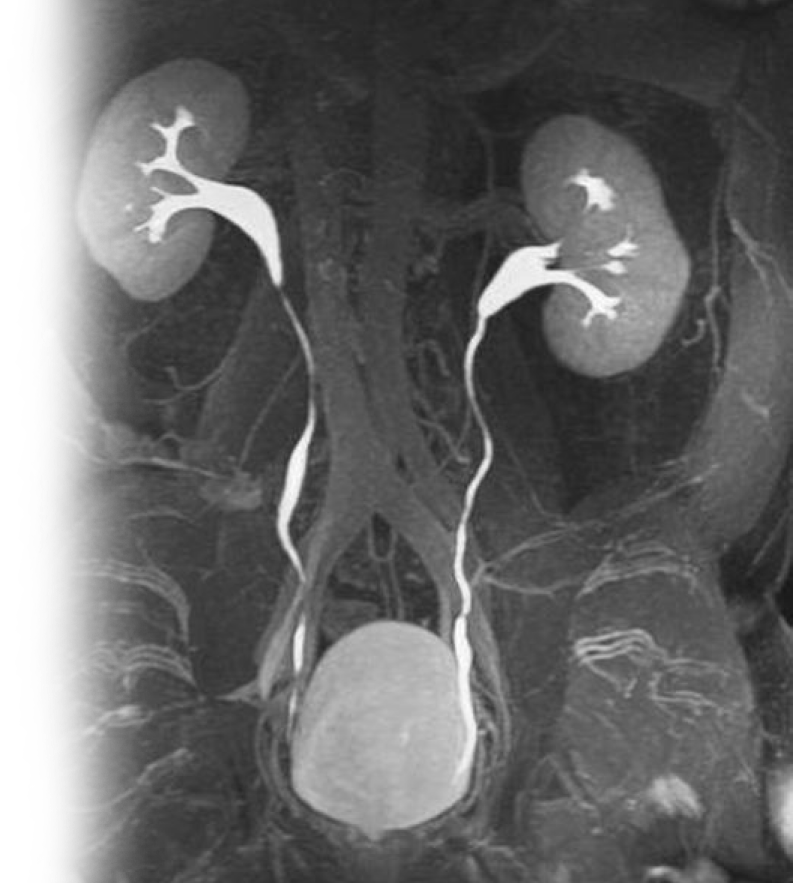

МР контрастная урография

МР контрастная урография – важный метод исследования с применением контрастирующего вещества, который позволяет визуализировать лоханки и мочеточники, паренхимы почек и окружающих мягких тканей.